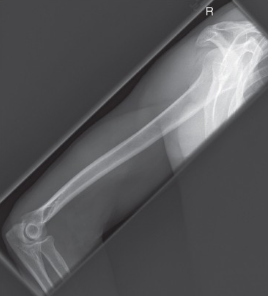

name the position

horizontal beam lateral (distal humerus)

evaluation criteria for horizontal beam lateral (distal humerus) position

distal 2/3 of humerus and elbow demonstrated

epicondyles superimposed